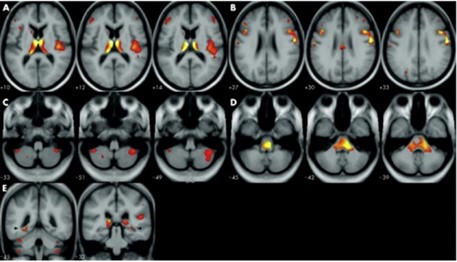

A propósito de lo anterior, una investigación realizó un análisis sistemático sobre estudios de tomografía por emisión de positrones (TEP) y resonancia magnética funcional (RMf) centradas en la CPF en relación con adicciones. Se incluyó la corteza orbitofrontal (COF), la corteza cingulada anterior (CAA) y la corteza prefrontal dorsolateral (CPFDL).(7)

En este estudio que se viene comentando, las áreas de la CPF muestran diferencias actividades entre individuos con adicción y casos controles saludables durante tareas que involucran atención y memoria de trabajo (verde), toma de decisiones (azul claro), control inhibitorio (amarillo), emoción y motivación (rojo) y la reactividad de la señal y la administración del fármaco (naranja). Además, en algunas áreas de la CPF, la actividad se correlaciona con el desempeño de la tarea o el uso de drogas (azul oscuro)(7) (ver Imagen 4-a).

De igual forma, en este mismo estudio se evidenciaron cambios en la actividad cerebral relacionados con las características clínicas de la adicción, incluida la intoxicación y los atracones (rojo, considerando que las drogas se usaron dentro de las 48 horas posteriores al estudio), la ansiedad (rosa, las drogas se usaron una o dos semanas antes del estudio) y la abstinencia (púrpura, los medicamentos se usaron más de tres semanas antes del estudio(7) (ver Imagen 4-b).